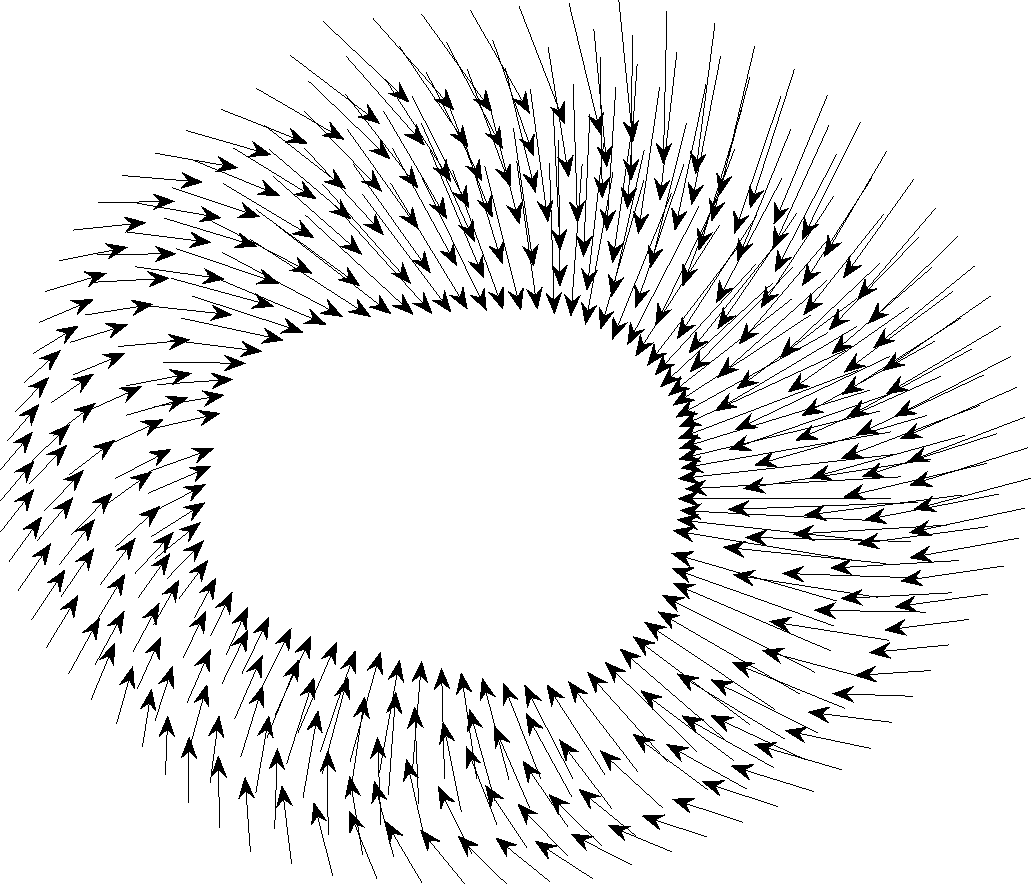

Inner and outer contours in MRI images are determined with hand by [23]. Each contour consists of 32 points. The goal here is to find the one-to-one correspondence between contour points between frames. The resolution of the data points is increased by interpolation. Another thing to consider here is that the deformation of heart muscle is not only a concentric radial deformation, but it also contains rotation. On average, during systole, the cardiac muscle has a 7 degree clockwise rotation which needs to be considered in finding one-to-one correspondence and displacement vectors’ computation. The contour points are then down-sampled to reduce the computational complexity. Fig. 8 displays the displacement vectors of one slice of MRI data for subjects 23 (b) and 18 (a) during systole. The existence of MI has a visible effect on the deformation of cardiac muscle.